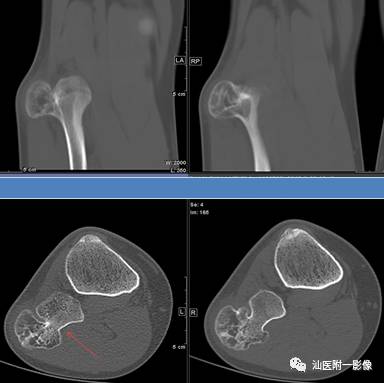

5.奇异性骨旁骨软骨瘤样增生 (新增)

•奇异性骨旁骨软骨瘤样增生(BPOP),又称Nora病(NL),是一种较为少见的良性骨膜外增生性病变。

•最常发生于40岁左右,无性别差异。50%复发。

•主要位于手、足短骨旁(中/近节指/趾骨、掌骨、跖骨居多)。

引自:徐恒天,焦俊,段庆红,等.Nora病的影像与病理对照分析[J].临床放射学杂志,2016,35(10):1608-1611.